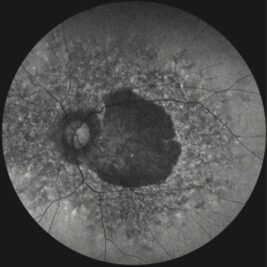

A key milestone is the EyeConic Study, a global multicenter ocular imaging initiative conducted in collaboration with more than 15 international clinical sites. EyeConic systematically characterises residual retinal structure in patients with inherited retinal degenerations (IRDs). Using AI-based image analysis, EyeConic demonstrated that a significant proportion of patients with generalised IRDs retain preserved foveal tissue, even in advanced disease stages. This finding closes a major knowledge gap and provides strong evidence supporting the feasibility of photoreceptor-targeted vision restoration therapies.

• EyeConic-GA: Investigating residual retinal structure in Geographic Atrophy (GA) due to age-related macular degeneration to evaluate the potential for vision restoration therapies.